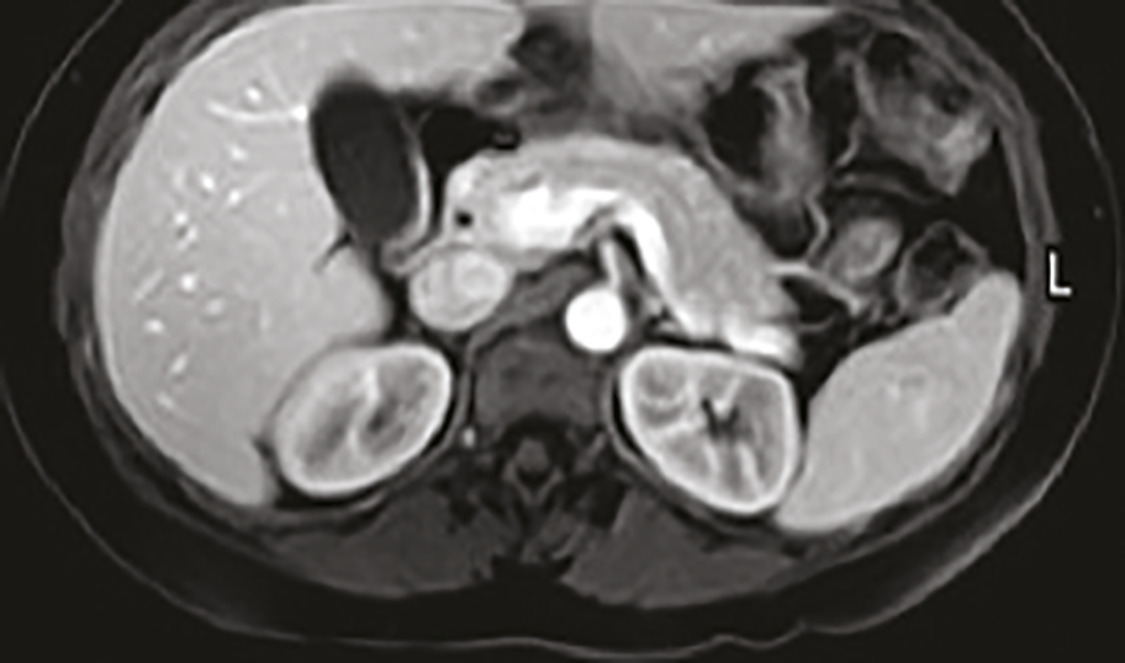

Cet homme de 53 ans suivi pour un syndrome anxiodépressif et un alcoolisme sevré, consultait pour une asthénie et un « burn-out ». L’interrogatoire notait que la fatigue s’estompait les week-ends et durant les vacances, et ne rapportait pas d’autre plainte fonctionnelle. Une biologie antérieure montrait une cytolyse hépatique prédominant sur les alanine aminotransférases (1,5 fois la valeur normale). Dans ce contexte, un bilan systématique était prescrit avec un contrôle thyroïdien et ferrique, montrant une hyperferritinémie à 3 756 µg/L. Le bilan complémentaire notait un coefficient de saturation de la transferrine (CST) à 90 %, une surcharge ferrique hépatique en imagerie par résonance magnétique (IRM, fig. 1 et 2 ) à 392 µmol/g, et une mutation postive C282Y homozygote. Le diagnostic d’hémochromatose héréditaire a été annoncé au patient au cours d’une consultation dédiée, en lui expliquant la nécessité d’une saignée hebdomadaire avec comme objectif une ferritinémie inférieure à 50 µg/L et l’intérêt d’un dépistage familial. L’évolution est marquée par une stabilisation de l’asthénie permettant à ce patient sportif une reprise partielle de ses activités physiques.

L’asthénie est un motif fréquent de consultation en médecine générale.1 Il n’existe pas de recommandations pour un bilan type. Un examen clinique précis vise à ne proposer un bilan qu’aux patients suspects d’une maladie sous-jacente, tels que notre patient ayant une anomalie du bilan hépatique. L’hémochromatose liée au gène HFE (type 1)2 est une maladie génétique de surcharge en fer (mutation C282Y). Le retard diagnostique est fréquent, devant des symptômes peu spécifiques, mais un diagnostic précoce permet de mieux prévenir les complications. Le CST et l’IRM sont les examens de référence. Les facteurs de risque de survenue d’une complication sont la consommation d’alcool et les viroses hépatotropes. Le traitement repose sur des saignées.